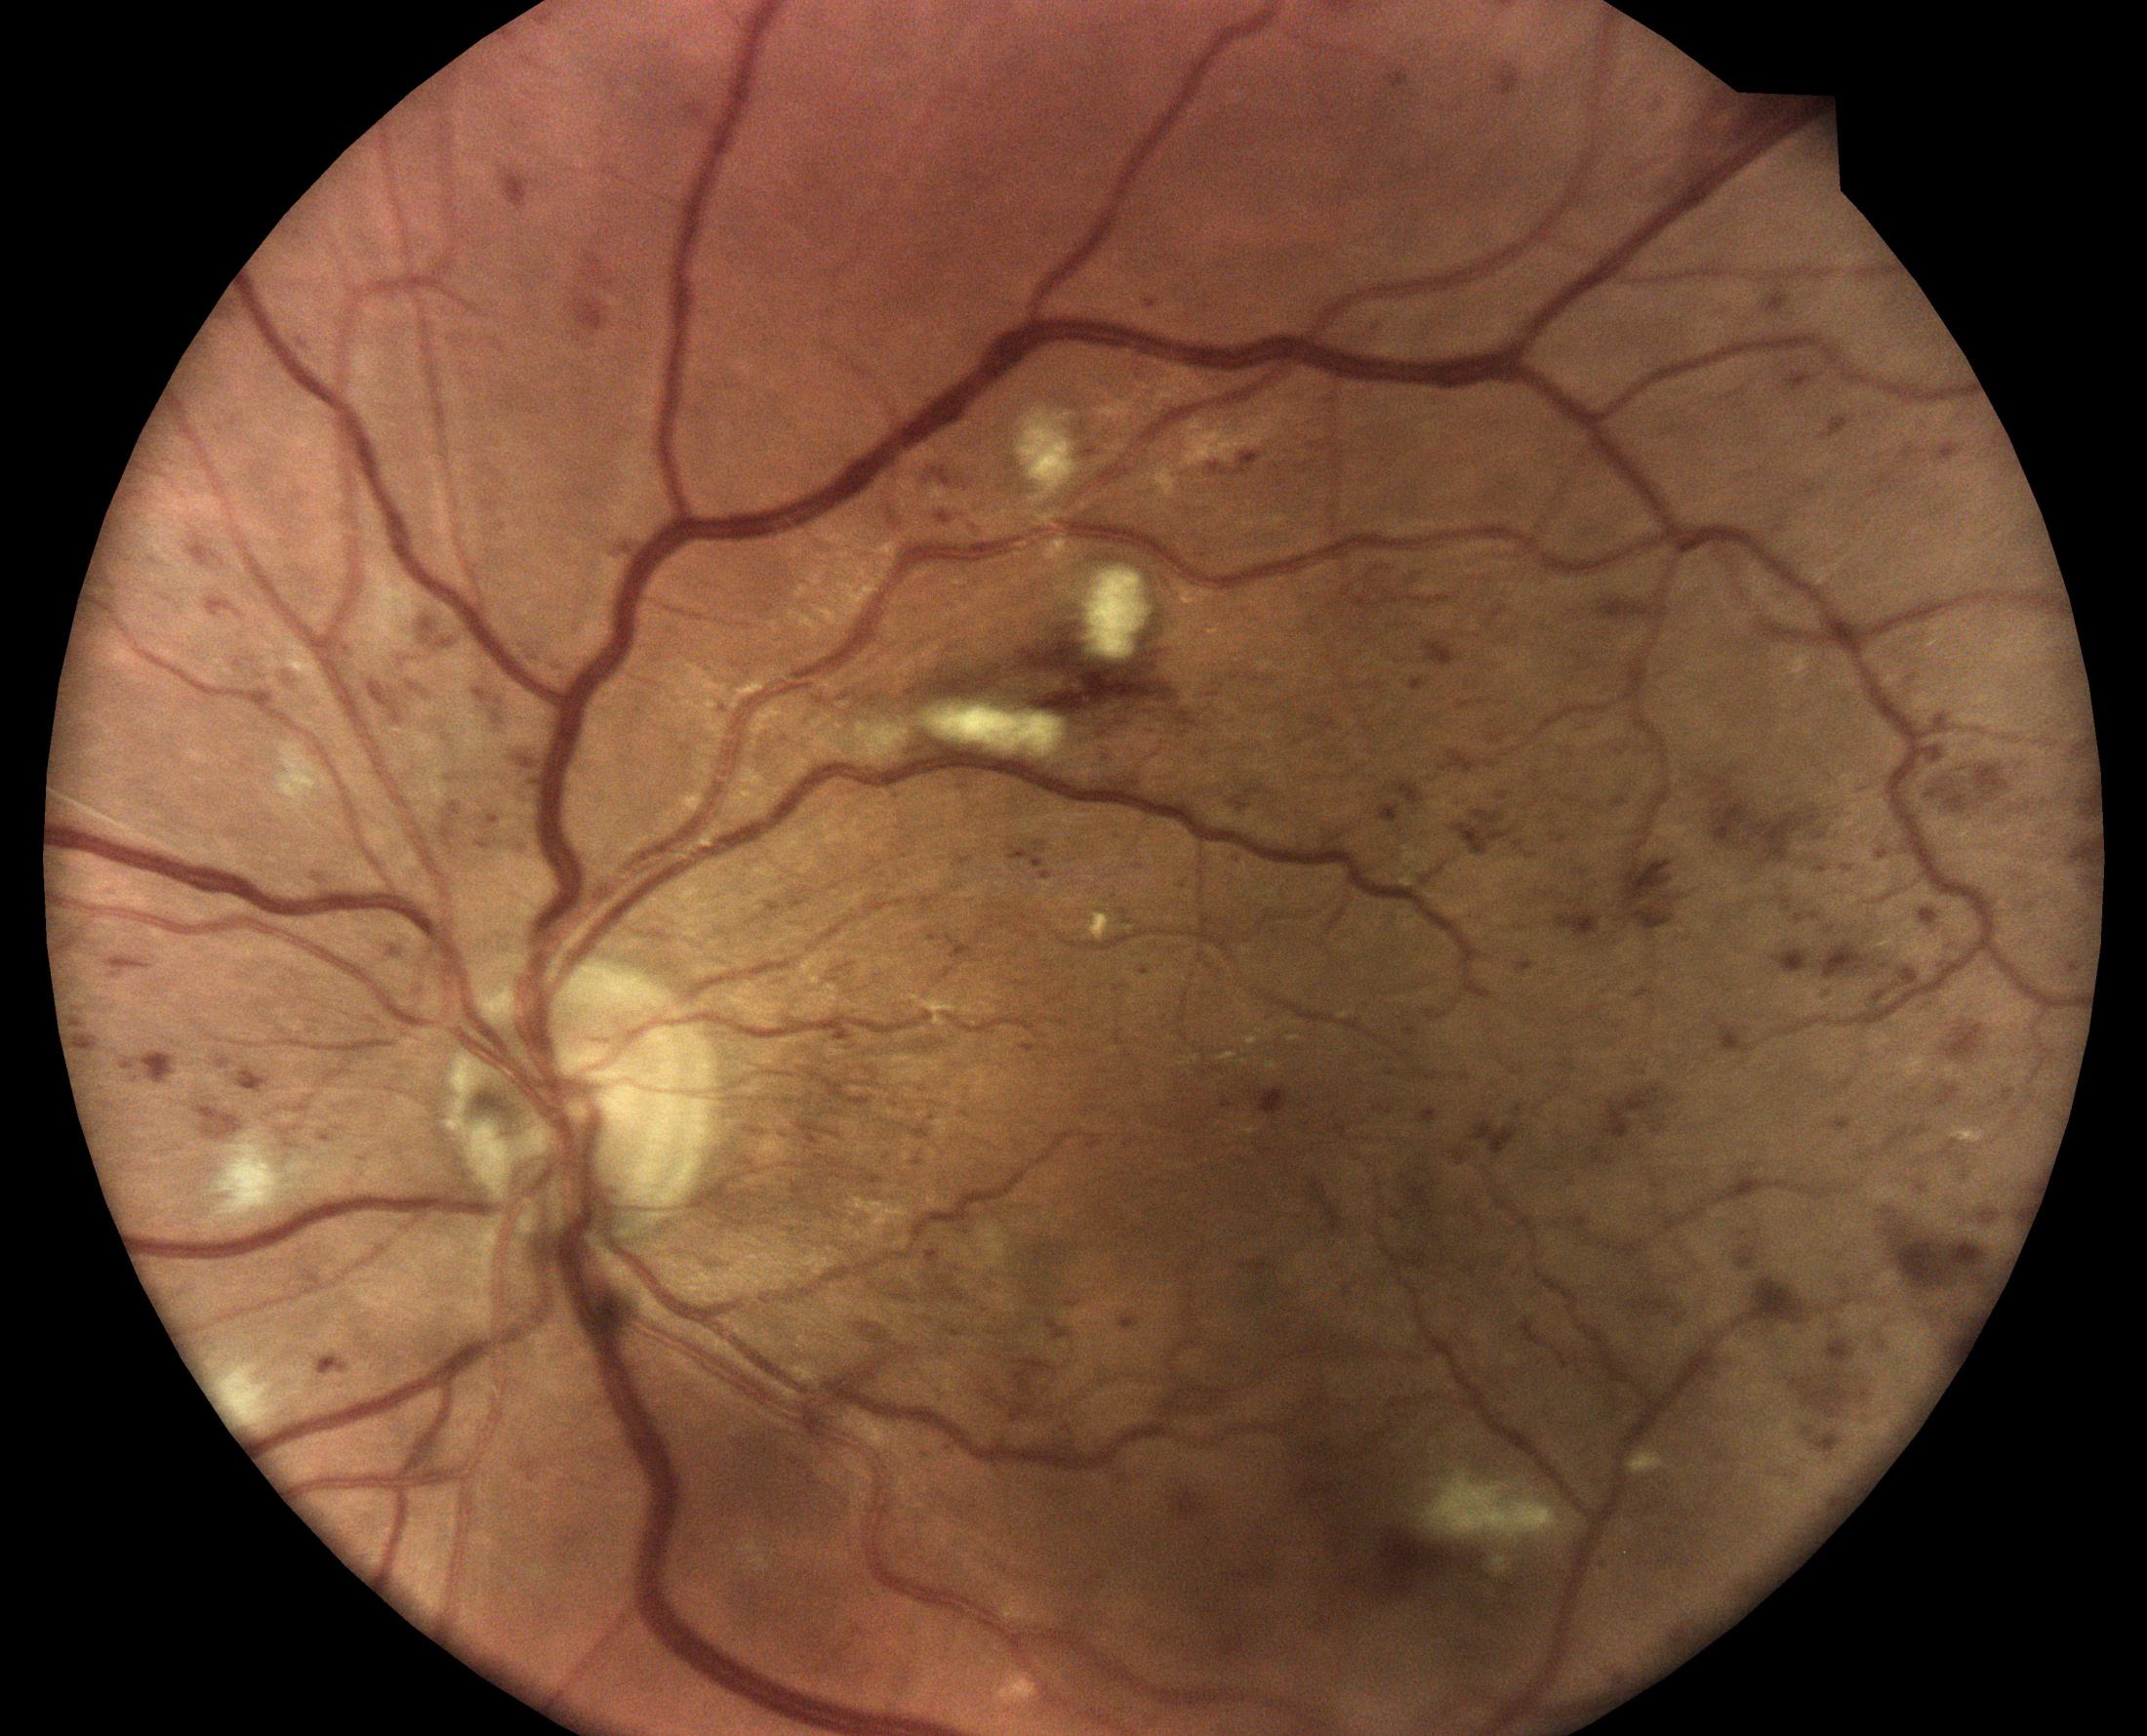

Konfokálny zobrazovací systém fundus iCare DRSplus využíva biele LED osvetlenie, ktoré ponúka vysoko kvalitné snímky TrueColor. Technológia TrueColor Confocal, ktorú je možné považovať za štandard vysokej kvality obrazu, poskytuje snímky sietnice špičkovej kvality, bohaté na detaily s vyššou ostrosťou obrazu, optickým rozlíšením a kontrastom v porovnaní s tradičným zobrazovaním očných kamier, efektívnym, automatizovaným procesom bez potreby dilatácie. Presná dokumentácia vo verných farbách poskytuje zdravotníkom jasný, autentický pohľad na očné pozadie vrátane tých najmenších detailov. Toto intuitívne a užívateľsky jednoduché zariadenie DRSplus umožňuje nielen očným lekárom venovať pozornosť detekcii, diagnostike a liečbe patológií.

Rôzne zobrazovacie možnosti pre bohaté a detailné zobrazenie

Technológia TrueColor Confocal s bielou LED, podporuje detailné 45° snímky sietnice a umožňuje skenovanie cez šedý zákal, aby pomohla lekárom pri diagnostike a dokumentácii očných chorôb. Technologickým jadrom DRSplus je jedinečná technológia TrueColor Confocal od iCare, jedinečná kombinácia konfokálnej optiky a bieleho LED svetla. Táto bezprecedentná kvalita obrazu je osvedčená najmä v náročných diagnostických situáciách, ako je hodnotenie pacientov s malými zreničkami alebo šedými záklami. Tradičné systémy na zobrazovanie sú citlivé na opacity - nepriehľadnosť, ktoré majú často tendenciu odrážať svetlo späť do kamery. To robí problém pri získavaní jasných snímok sietnice za nepriehľadnám pozadím.

Lúč svetla na konfokálnom optickom prístroji je veľmi zaostrený, úzky a presný. To umožňuje DRSplus vyprodukovať vysokokvalitné snímky aj v prípadoch, keď je pohľad na sietnicu blokovaný šedým zákalom alebo inými záklami.

Filtrovanie bez červenej s vysokým rozlíšením zlepšuje vizualizáciu vaskulatúry sietnice, modré obrázky poskytujú lepší pohľad na vrstvu nervových vlákien (RNFL) a červený kanál umožňuje svetlu prenikať do hlbokých vrstiev sietnice. Infračervené svetlo poskytuje podrobné informácie zodpovedajúce cievam. Externé zobrazenie oka môže dokumentovať stav povrchu oka a rohovky. Technológia stereo zobrazovača vytvára vylepšené 3D vnímanie disku. Možnosť funcie mozaiky automaticky kombinuje rôzne polia sietnice bez zásahu používateľa a vytvára panoramatické pohľady až do 80 stupňov.

Technológia True Color Confocal

Technológia TrueColor Confocal s bielou LED, podporuje detailné 45° snímky sietnice a umožňuje skenovanie cez šedý zákal, aby pomohla lekárom pri diagnostike a dokumentácii očných chorôb. Jasne osvetlené prostredie a niektoré farmakologické liečby spôsobujú, že sa zrenička zmenší na veľmi malú veľkosť. To predstavuje výzvu pre tradičné zobrazovacie systémy - oční lekári zvyčajne potrebujú byť v tmavej miestnosti alebo dilatovať, aby mohli získať adekvátne snímky sietnice. Napríklad tradičnými fundus kamerami je ťažké získať jasný obraz cez zreničky menšie ako 3,5 mm. DRSplus však vytvára vysokokvalitné snímky sietnice v prirodzených farbách cez zrenice až do veľkosti priemeru min. 2,5 mm. To znamená, že snímky je možné nasnímať úplne bez dilatície pri jasnom svetle , čo ušetrí očnému lekárovi značné množstvo času a úsilia.

Bežné fotoaparáty s bleskom zachytávajú farebné snímky sietnice, ktorých kvalita môže byť ovplyvnená prítomnosťou zákalu (ako je šedý zákal, alebo zákal rohovky), nečistotami na šošovkách zariadenia, malým priemerom zreníc a vrstvami očného pozadia, ktoré sa líšia od samotnej sietnice (tj. choroidálny spätný rozptyl). Vásledkom je obraz sietnice, ktorý zvyčajne vyzerá plocho, preexponovaný v červenom kanály, s vyblednutými oblasťami a s celkovo nižším rozlíšením a nižším kontrastom, než aké je možné dosiahnuť pomocou konfokálneho optického mechanizmu.

V porovnaní s tradičnými riešeniami ponúka technológia TrueColor Confocal od iCare vylepšenú kvalitu obrazu, vylepšený kontrast, jemnejší detailný obraz, potlačenie rozptýleného svetla a lepšie zobrazenie pacientov so slabou dilatáciou spoločne so širokým bohatým farebným rozsahom a vysokou vernosťou farieb.